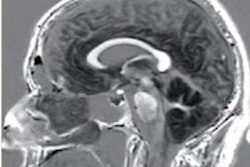

(a) Schematic illustration of International Federation of Gynaecology and Obstetrics (FIGO) stage I. Axial T2-weighted image (b), axial fat saturation T2-weighted image (c) and diffusion-weighted imaging with b-value = 800 s/mm2. (d) shows a vulvar tumor measuring < 2 cm, with pathologic proven stromal invasion of 4 mm, corresponding to FIGO stage IB. All images courtesy of Dr. Olivera Nikolić and Insights into Imaging."In spite of that, MRI staging of vulvar cancer is not used routinely in all cancer centres," the group's chair, Dr. Olivera Nikolić of the University of Novi Sad, Serbia, and colleagues wrote in an article published on 22 September in Insights into Imaging. "Standardising image acquisition techniques and MRI interpretation reduces ambiguity and ultimately improves the contribution of radiology to the staging and management of patients with vulvar cancer."